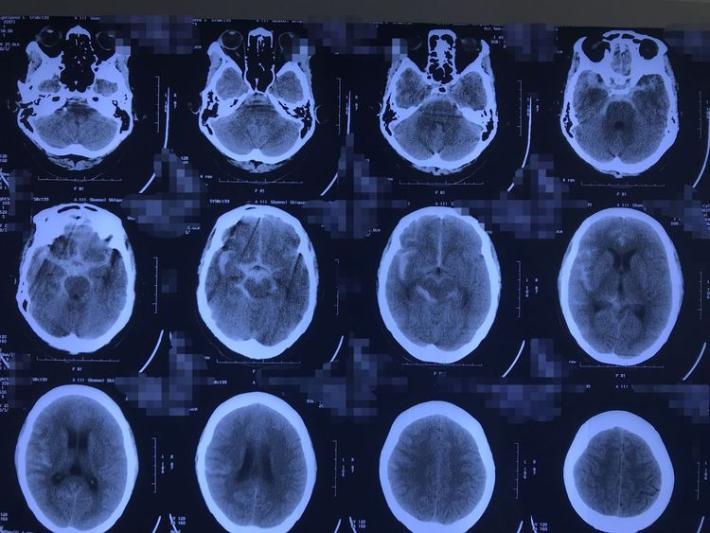

发病当日外院CT示蛛网膜下腔出血

术后CT示术野干净,无出血或梗塞。